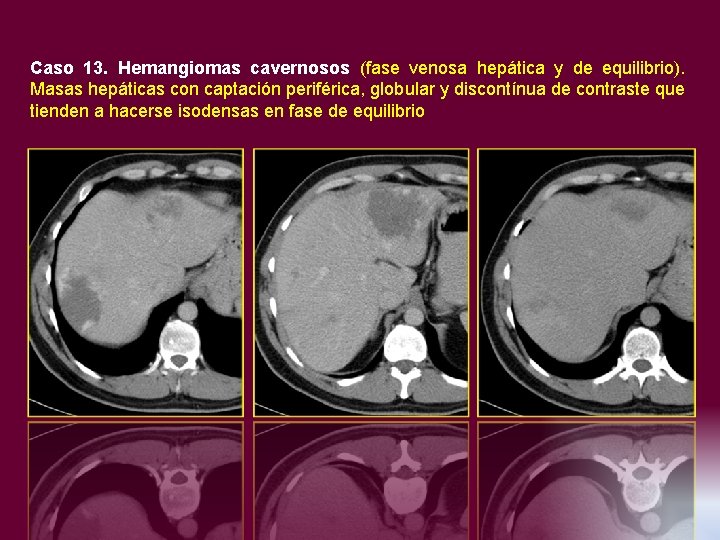

Caso 13. Hemangiomas cavernosos (fase venosa hepática y de equilibrio). Masas hepáticas con captación

Caso 13. Hemangiomas cavernosos (fase venosa hepática y de equilibrio). Masas hepáticas con captación periférica, globular y discontínua de contraste que tienden a hacerse isodensas en fase de equilibrio